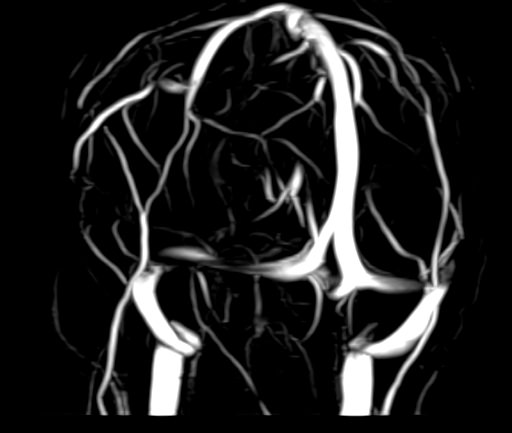

Магнитно-резонансная венография головного мозга позволяет детально изучить особенности анатомического и функциональной состояния венозного русла головного мозга. С помощью данного исследования можно исключить многие серьезные заболевания сосудов головного мозга и начать своевременное лечение.

Магнитно-резонансная томография вен применяется для диагностики широкого ряда заболеваний. В основе метода лежит воздействие магнитного излучения на ткани человека, что абсолютно безопасно и дает возможность с точностью визуализировать строение сосудов головного мозга.

По информативности МРТ артерий и вен головного мозга на шаг опережает традиционные способы диагностики с применением рентгеновских лучей или ультразвука. На МР-изображениях врачи-диагносты получают наглядную информацию о функционировании вен головного мозга.

МР-венография позволяет с высокой точностью определить:

• анатомический рисунок венозной системы;

• врожденные и приобретенные отклонения в строении и функционировании сосудов;

• нарушения трофики и оттока крови от отделов мозга;

• возможные повреждения сосудов и их последствия;

• наличие опухолевых образований, перекрывающих сосудистое русло.